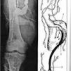

Аневризма бедренной артерии определяется в виде пульсирующею опухолевидного образования в проекции бедренной артерии.